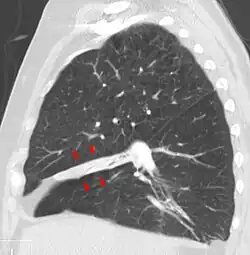

| Atelectasis of a person's right lung | |

Clinically significant atelectasis is generally visible on chest X-ray; findings can include lung opacification and/or loss of lung volume. Post-surgical atelectasis will be bibasal in pattern. Chest CT or bronchoscopy may be necessary if the cause of atelectasis is not clinically apparent. Direct signs of atelectasis include displacement of interlobar fissures and mobile structures within the thorax, overinflation of the unaffected ipsilateral lobe or contralateral lung, and opacification of the collapsed lobe. In addition to clinically significant findings on chest X-rays, patients may present with indirect signs and symptoms such as elevation of the diaphragm, shifting of the trachea, heart and mediastinum; displacement of the hilus and shifting granulomas.[13]